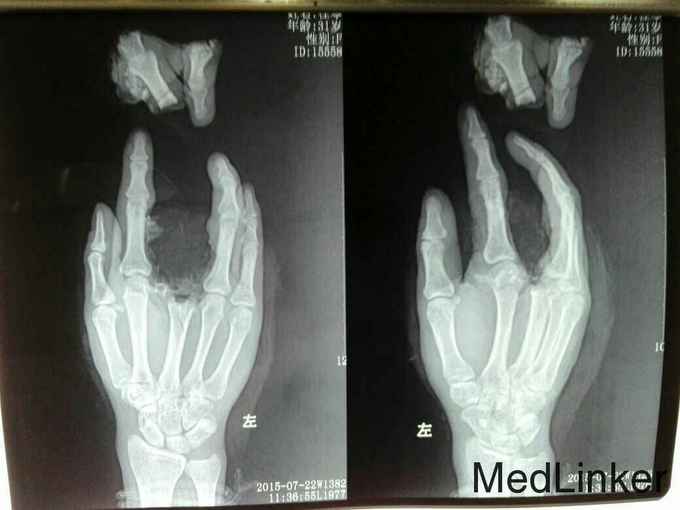

左中指两平面离断再植。

左中指于第3掌骨及近指间关节完全离断,行再植术。